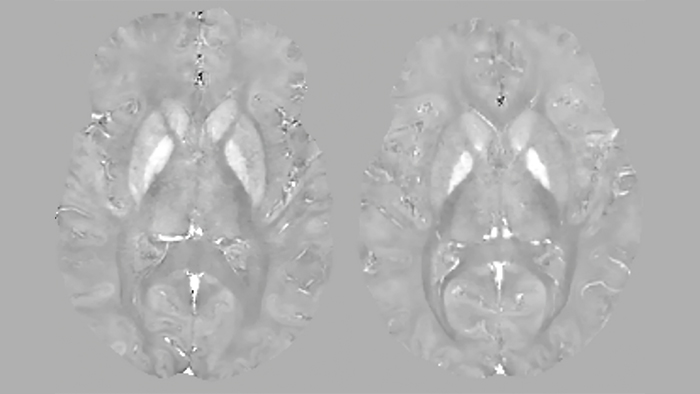

В случае T1-картирования с введением контраста, на получаемых картах зоны ПИКС выделяются на фоне здорового миокарда за счет повышенного накопления в них контрастного агента, который сокращает время T1. На рис. 9 видны области пониженного значения T1, соответствующие фиброзу в результате инфаркта. Слева - рубцовые изменения по нижней стенке левого желудочка, справа - рубцовые изменения в 7, 8 и частично 9 сегментах (согласно разработанной Американской кардиологической ассоциацией 17-сегментной модели сердца [19].